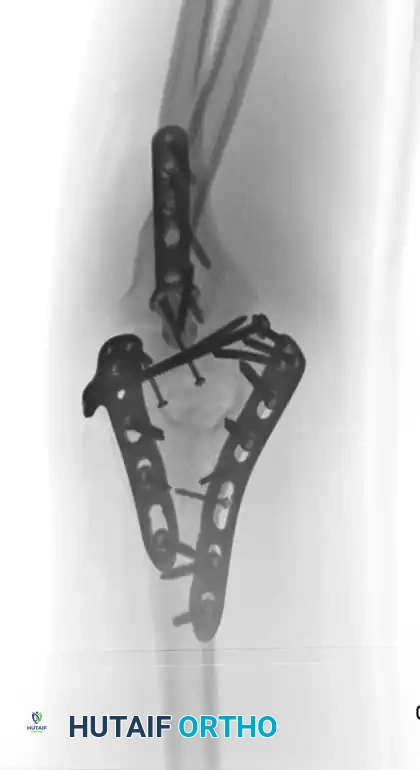

Plating Configurations: Orthogonal vs. Parallel

Historically, the standard technique involved placing plates at orthogonal angles (90-90 plating), typically with a medial plate applied to the medial ridge and a lateral plate applied to the posterior surface of the lateral column.

Image

Fig. 3: Supracondylar fracture with intra-articular extension fixed with 90-90 locked plates through an olecranon osteotomy approach, and subsequent hardware removal.